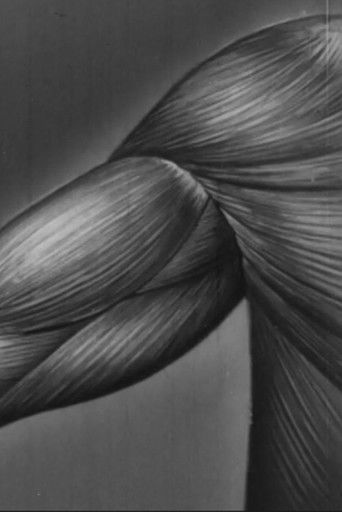

Part two of two teaching films about human anatomy which is devoted to the action of the skeletal muscles in producing movement of the bones at the joints of the human skeleton. It uses live action and animated medical illustrations as well as an actual skeleton with commentary. A man, naked to the waist, also demonstrates the relevant physical processes such as respiration.